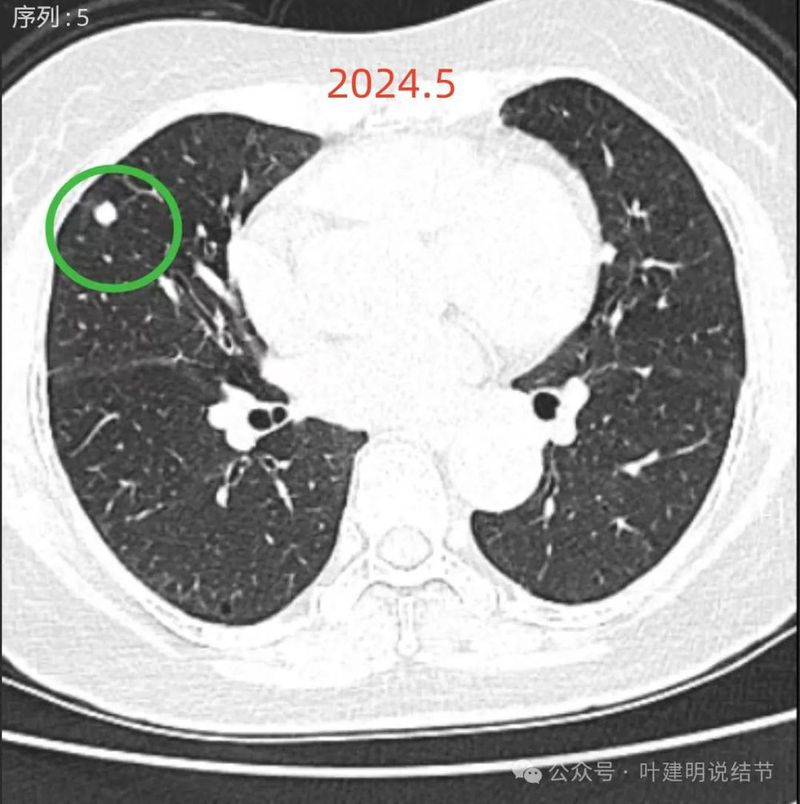

再看2024年5月时的影像:

病灶9:右中叶实性结节,较2021年无明显进展,考虑良性可能性大些;

两肺多发磨玻璃结节,部分是混合密度。主病灶是红色这处在左上叶的,对比2021年有明显增大进展,考虑是浸润性腺癌可能性大,或者微浸润性腺癌;粉色的考虑原位癌可能性大;橘色的考虑不典型增生可能性大;黄色的考虑肺泡上皮增生可能性大;紫色的考虑微浸润性腺癌可能性大;绿色的考虑良性的可能性大;蓝色的考虑浸润性腺癌或者微浸润性腺癌;黑色的是2021年的时候比较明显的几处病灶。总体对比来看红色的范围增大比较明显,实性成分也有增加;蓝色的密度增加比较明显。首先考虑是多原发早期肺癌。个人觉得继续随访存在一定风险,当然由于病灶太多,也不是说都靠外科手术能够解决问题的,但是主要的有风险的病灶如果能够手术还是需要手术先解决,其他次要的病灶后续再考虑消融或者其他治疗。我的想法是先做右肺下叶背段切除(紫色,考虑微浸润或浸润)加上叶楔形切除(蓝色),下叶粉色的也可楔切或不切;之后看恢复情况过三个月左右再做左肺上叶切除。其余病灶后续如果随访进展考虑消融控制。意见供参考!为何先建议做右侧:先做右侧是因为右侧切得少,到时候再切左侧的时候,单肺通气更能耐受。如果先做左侧,下次做右侧时,左下叶单肺通气不太能耐受些。而且蓝色这处密度增加明显,又贴着胸膜,它的风险相对来说也较高,或许比左上红色的还高点。所以先做右侧。若非转移,靶向药个人不太建议吃,又不是晚期,是多原发早期肺癌可能性大呀。